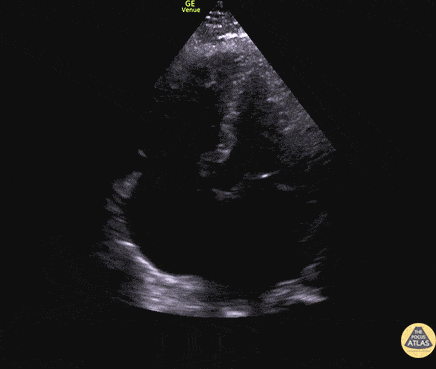

Left Ventricular Dysfunction - Biventricular Failure Apical 4

50 y/o M PMH methamphetamine abuse presents in respiratory failure with cool, mottled skin and poor capillary refill. Patient was tachycardic, hypothermic with multiple signs of end organ dysfunction. POCUS quickly narrowed the differential by demonstrating clear, severe, reduced ejection fraction by visual estimation and a plethoric IVC without respiratory variation. Patient was ultimately started on dobutamine and transferred to the MICU for treatment of cardiogenic shock. Dr. Jaclyn Walker, Dr. Matthew Riscinti - Denver Health Emergency Medicine